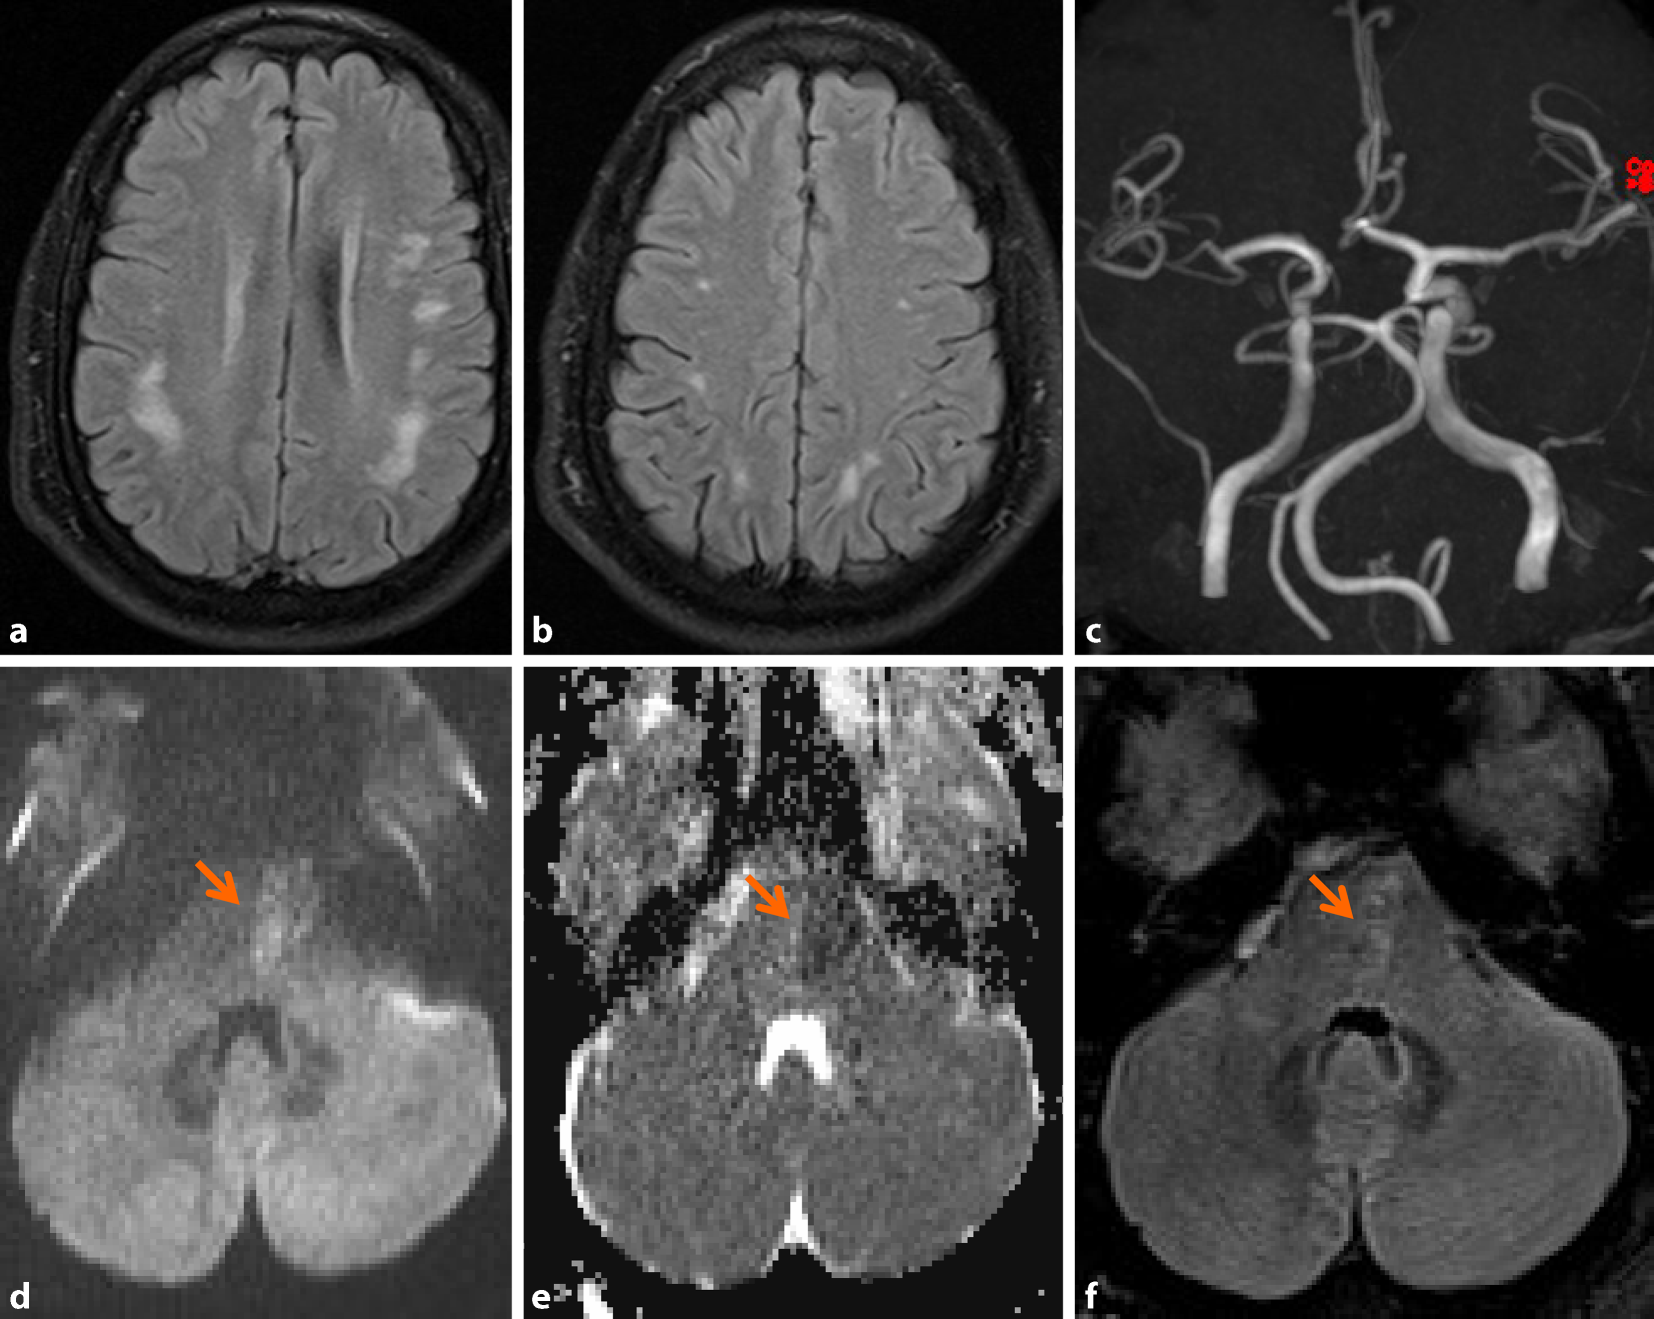

Aufgrund der vorliegenden Befunde wurde der Verdacht auf eine ZNS-Vaskulitis gestellt; da der Patient keine Anzeichen für eine systemische Vaskulitis hatte (keine Gelenks- oder Hautaffektion, unauffälliger ophthalmologischer Status, unauffälliges Labor inkl. immunpathologischem Serumprofil), wurde von einer isolierten ZNS-Manifestation (primäre Angiitis des ZNS) ausgegangen. Dieser Verdacht konnte in einer digitalen Subtraktionsangiographie, in der sich multisegmentale leicht- bis mittelgradige Kaliberirregularitäten in Gefäßabschnitten 3. und 4. Ordnung nachweisen ließen (Abb. 2), erhärtet werden. Schließlich konnte die suspizierte Diagnose mittels Hirnbiopsie bestätigt werden.

Abb. 2

In der konventionellen Viergefäßangiographie zeigen sich leicht- bis mittelgradige Stenosierungen von Gefäßen 3. und 4. Ordnung in verschiedenen zerebrovaskulären Stromgebieten (a und b, Kreise). (© Univ.-Klinik für Radiologie, LKH Univ.-Klinikum Graz)